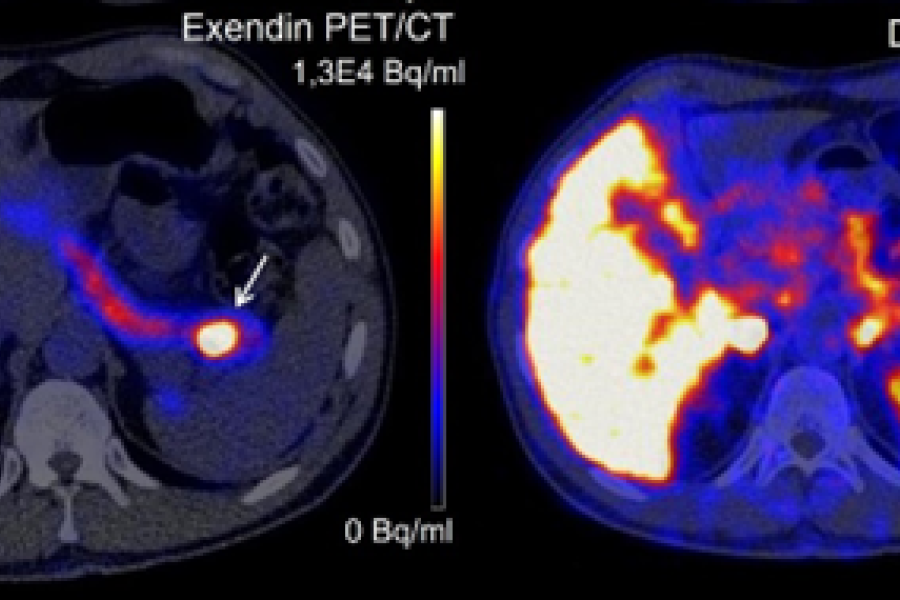

Catharina Ziekenhuis en TU/e ontvangen ruim 1,3 miljoen euro voor onderzoek naar alvleesklierkanker

december 16, 2025

EINDHOVEN – Het Catharina Ziekenhuis en de Technische Universiteit Eindhoven (TU/e) hebben van KWF Kankerbestrijding financiering van 1.331.931,50 euro ontvangen voor een innovatief onderzoek naar het vroegtijdig opsporen van alvleesklierkanker met behulp van kunstmatige intelligentie (AI). Het onderzoek, dat de komende vijf jaar wordt uitgevoerd onder leiding van hoogleraar en oncologisch chirurg Misha Luyer, richt […]

Diagnostiek bij alvleesklierkanker verbetert met behulp van AI

november 24, 2025

Onderzoekers ontwikkelen betrouwbare dataset om de het beste AI-model vast te stellen De diagnostiek bij alvleesklierkanker verbetert als kunstmatige intelligentie wordt ingezet. AI spoort tumoren nauwkeuriger op dan de gemiddelde radioloog. Dat blijkt uit een internationale studie geleid door het Radboudumc, nu gepubliceerd in vakblad Lancet Oncology. De onderzoekers ontwikkelden een betrouwbare dataset, waarmee ze het […]